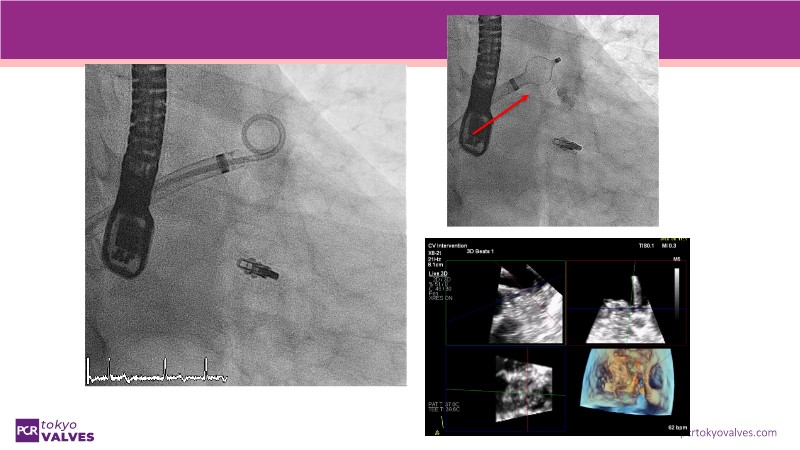

Explore the latest advancements in TEER therapy with this PCR Tokyo Valves 2025 session dedicated to MitraClip. Through expert-led case discussions, gain a deeper understanding of complex scenarios, including restricted posterior leaflet in functional mitral regurgitation, commissure lesion (A3P3), and MitraClip combined with Amulet.